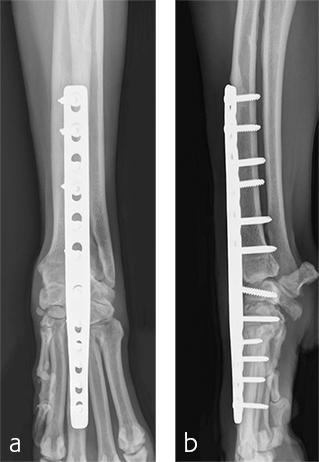

A custom fiberglass palmar splint was applied from the paw to just distal to the elbow after surgery. The splint was used for 4 weeks followed by a soft padded bandage for 4 weeks. Bandage changes were performed weekly. Activity was restricted to leash walks only for 12 weeks postoperatively. Radiographic examination 8 weeks after surgery revealed early healing of the pancarpal arthrodesis and stable implants. No complications were noted (Fig 6).

The patient was returned to normal activity 4 months after surgery. Radiographic examinations at 6 and 6.5 months after surgery revealed stable implants and fusion of the carpus (Fig 7 and 8). Functional outcome was excellent 1 year postoperatively. The patient had returned to full weight-bearing without lameness and the carpus was pain-free and stable.